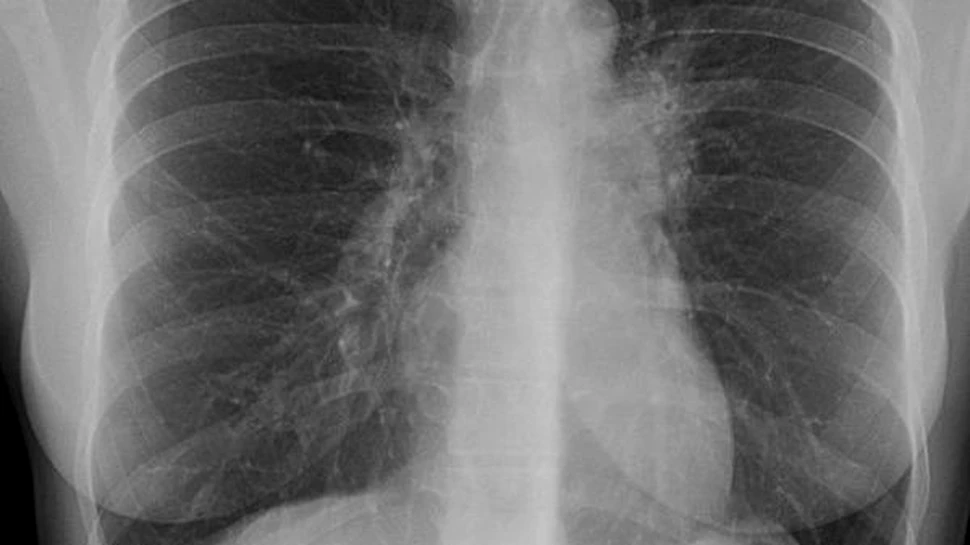

Medicii credeau ca au infrant-o in anii ’70, dar tuberculoza (TBC) s-a reintors, mai virulenta ca niciodata, cu formele sale rezistente la antibiotice si o “alianta” letala cu HIV. De aceasta data pare si mai periculoasa, poate si pentru faptul ca a fost subevaluata si aproape uitata de politicieni si de casele farmaceutice: 9 milioane de cazuri in fiecare an, aproape 2 milioane de morti si 2 miliarde de persoane infectate cu bacteria tuberculozei, adica o treime din populatia din Africa si Asia. “Mare parte din cazuri sunt concentrate in 22 de tari, toate cu nivelul veniturilor foarte scazut, iar in Africa subsahariana situatia este cu adevarat critica”, a declarat un reprezentat al Medicilor Fara Frontiere, organizatie internationala ce si-a propus sa readuca aceasta boala in lumina reflectoarelor (si eventual pe “masa” membrilor G8) prin intermediul campaniei “Tuberculoza: chipuri noi ale ale unei maladii vechi”.